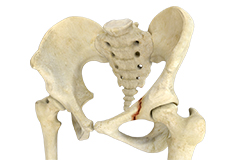

Avulsion Fractures of the Pelvis

Avulsion fractures of the pelvis is an injury that occurs when a tendon or ligament pulls off a piece of bone from the hip.